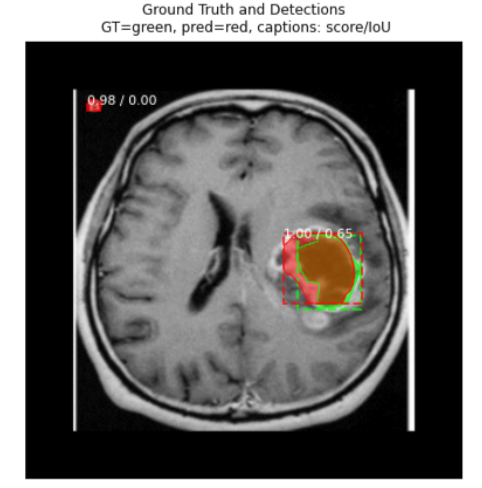

Test your model prediction on the validation set:

#Validation set

ind = 9

display_image(dataset_val, ind)

predict_and_plot_differences(dataset_val, ind)